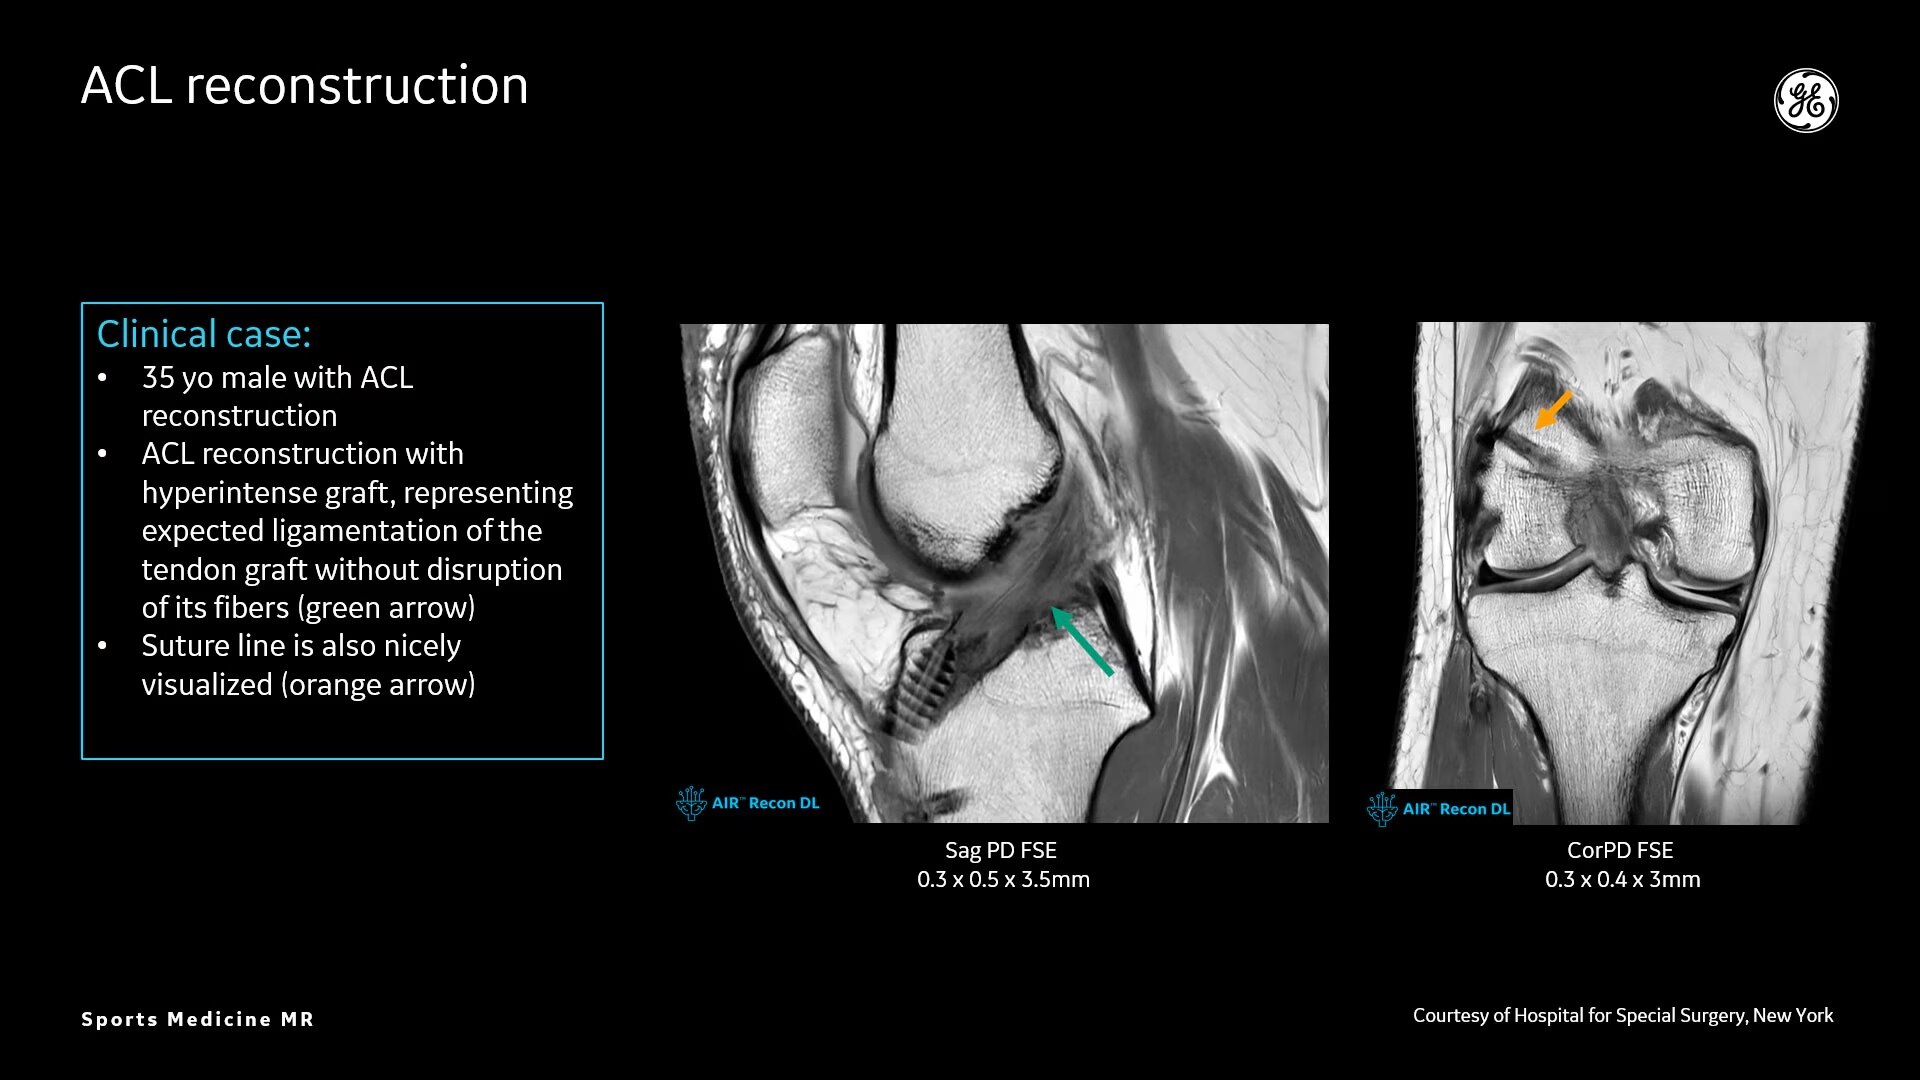

Sports Medicine Imaging

Deep-Learning MR Image Reconstruction Algorithm

High spatial resolution imaging

AIR™ Recon DL provides high-resolution images with increased SNR at markedly reduced scan times. This technology optimizes the depiction of even small injuries, such as meniscal, labral and ligament tears. The reduction in scan times increases flexibility for individually tailored MR protocols with an additional oZTEo sequence for detailed fracture assessment.